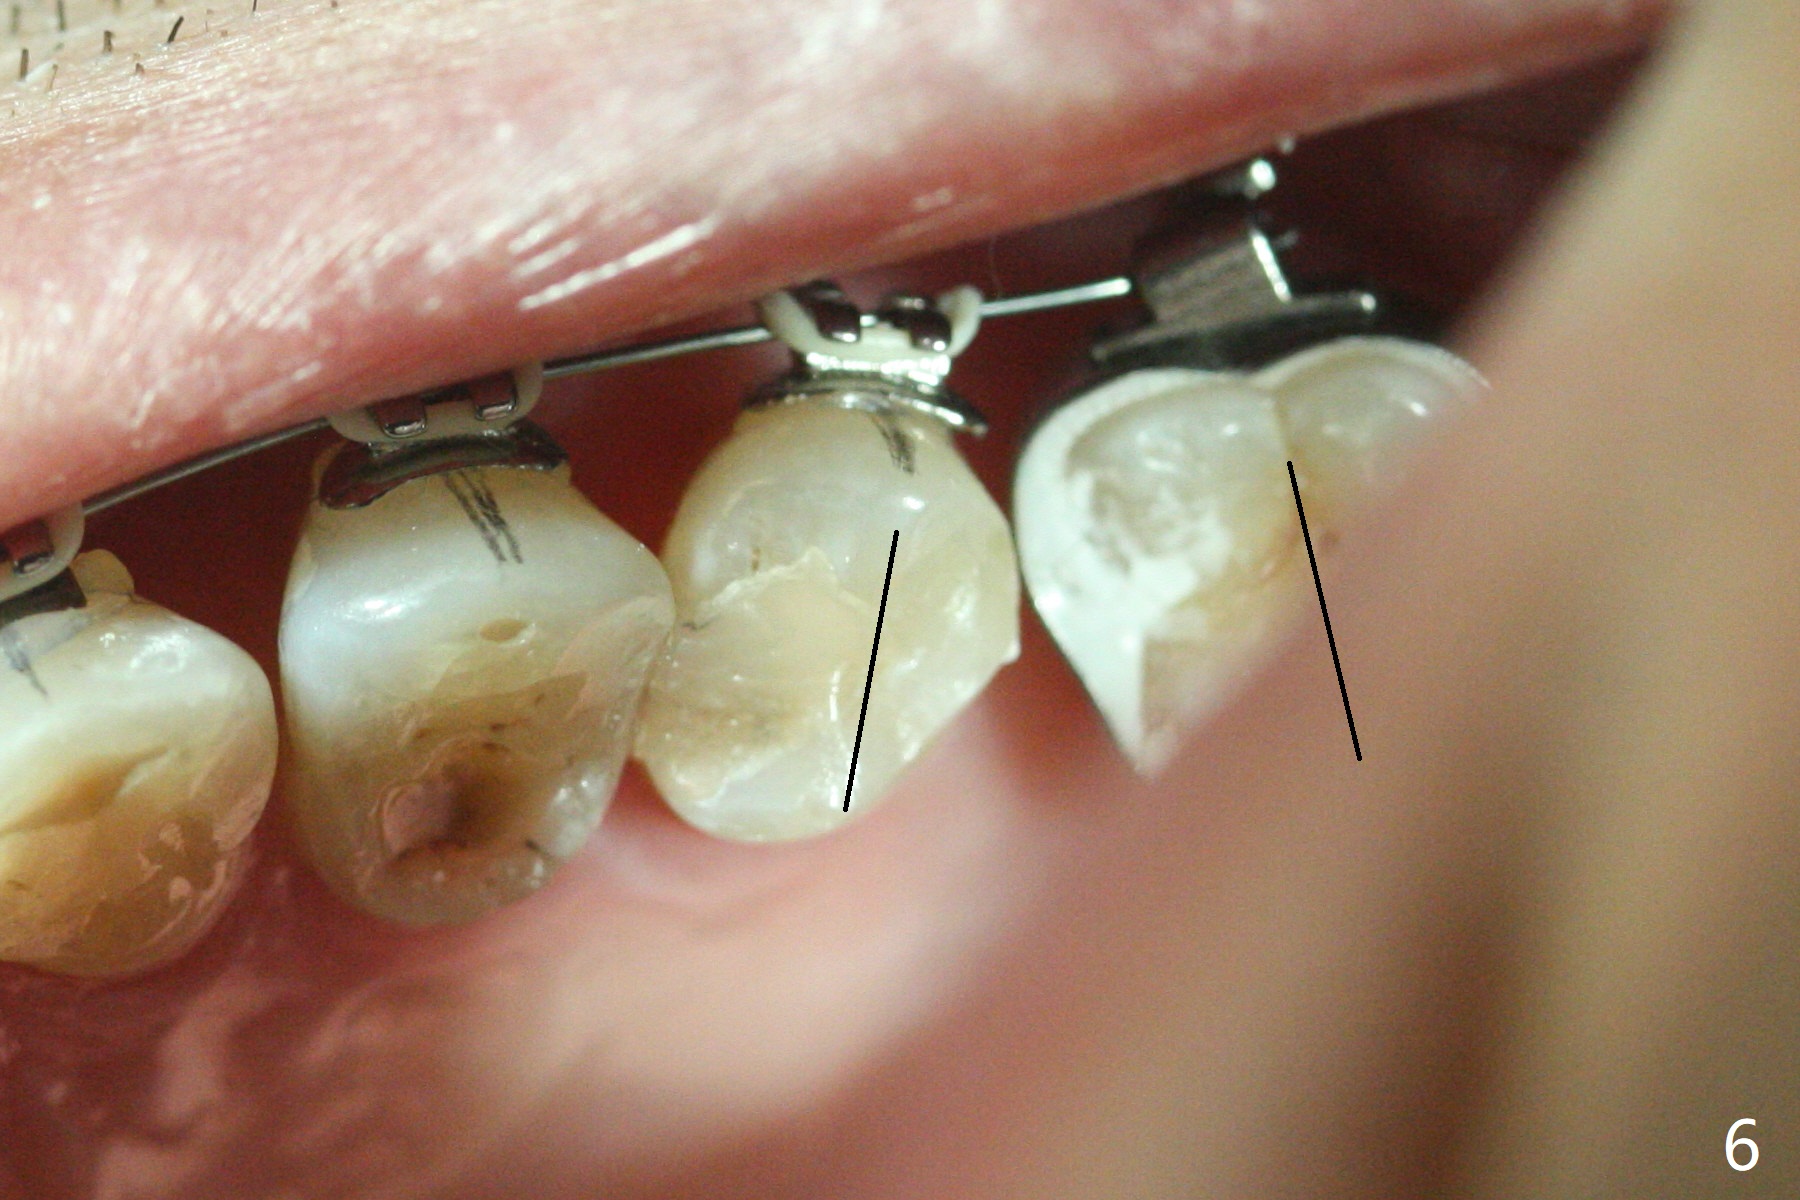

A 54-year-old man returns to office for UL7 upright 6 months post UR5 implant crown cementation (Fig.5,6). The ultimate purpose is to place implants at UL6 and LL 7. The latter will reduce severe occlusal wear especially in the lower anterior teeth (Fig.3,4). To solve the diastema between UR3 and 4 (Fig.1), the bracket at UR3 is placed in the height of contour (Fig.1 insert, Fig.4). Arch wire sequence may automatically close the diastema (Fig.1 insert arrows). In addition to tilting of UL7 (Fig.7), there are diastemata between U1s and UL3 and 4 (Fig.8,9 arrowheads). The patient is not tolerating orthodontic treatment well and requesting finishing the treatment early. We are considering mesializing UL7 instead of upright by placing a mini-implant between UL4 and 5 (Fig.10). There will be less interference of the roots of UL7 with the crown of the impacted UL8. There appears more space for a 1.6x8 mm mini-implant between UL4 and 5 (Fig.11) and UL 3 and 4 (Fig.12). Finally a mini implant is placed distal to UL7.